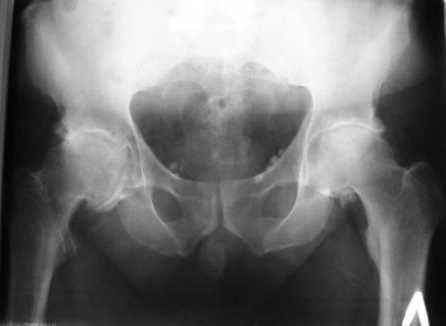

Больной Т. 56 лет, Диагноз: двухсторонний коксартроз 3-4 ст справа, 1-2 ст слева 2.10.08 выполнена операция тотальное бесцементное эндопротезирование. Использовался наружный доступ, положение на боку. Операция протекала без особенностей.

Выполнен послеоперационный ренгеноконтроль в прямой проекции. Рана зажила.

Больное выписан. Рекомендована ходьба без нагрузки 6 нед, рентгеноконтроль через 2 мес. Явка на консультацию На консультации через 7 недель- Больной ходит с дозированной нагрузкой, умеренные боли по задней поверхности правого бедра. Планируется ревизия. Удаление ножки. Установка такой же ножки Corail.